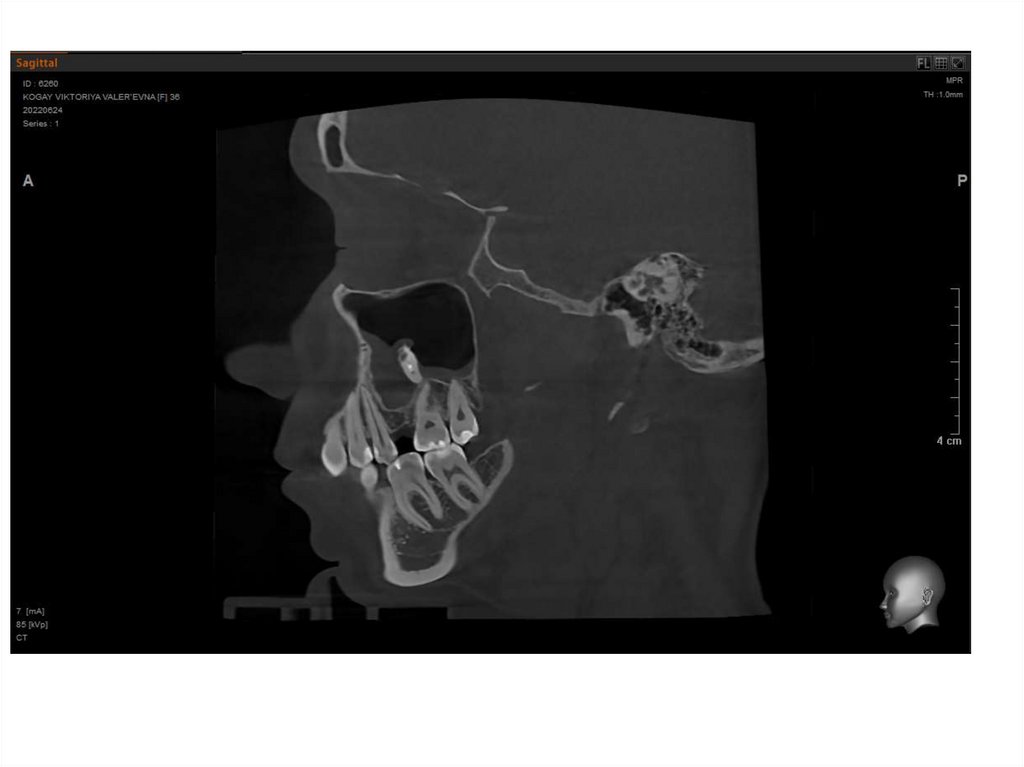

Когай Виктория Валерьевна

25.06.1985 ( 37 лет)

Дата консультации: 02.10.2022

Дата диагностики : слепки 02.10.2022

Снимок КТ 24.06.2022